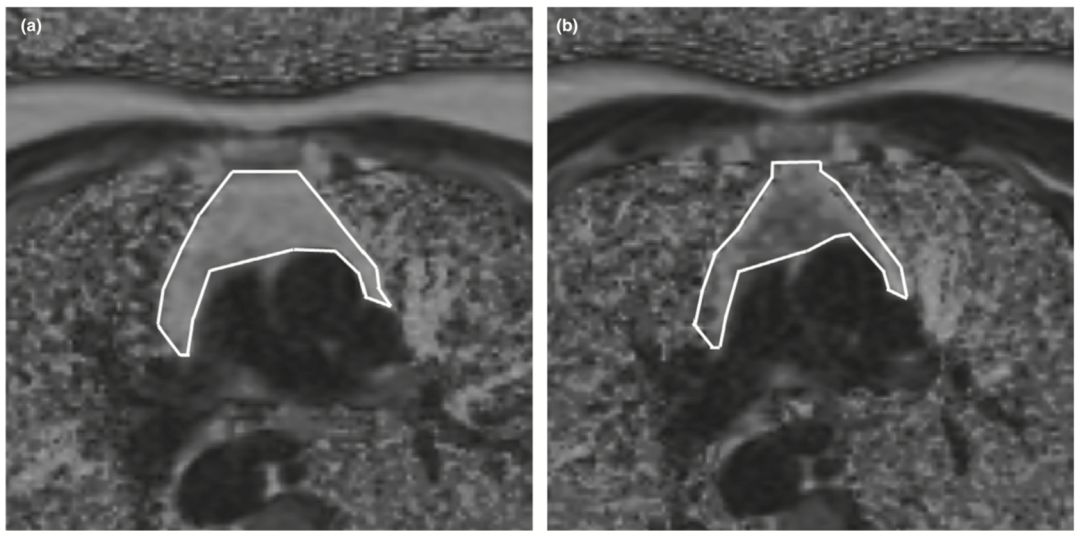

总体来看,整个研究是安全的,只有轻微的副作用,期间有1人因心动过缓退出试验。余下9人都顺利完成试验,胸腺的MRI密度明显改善,无脂肪分数显著增加,也就是说脂肪是减少了的。而且,有7名志愿者胸腺中累积的脂肪被再生的胸腺组织所取代。

▲ 治疗前的胸腺(a)脂肪多;治疗后的胸腺(b)脂肪少

此外,他们还观察到免疫细胞和细胞因子都在往好的方向发展。借助于Steve Horvath开发表观遗传学寿命预测方法,研究人员发现,接受一年的治疗之后,所有志愿者的平均生理年龄竟然比1年前还小了1.5岁,站在试验结束的时间来看的话,就是生理学年龄降低了2.5岁。